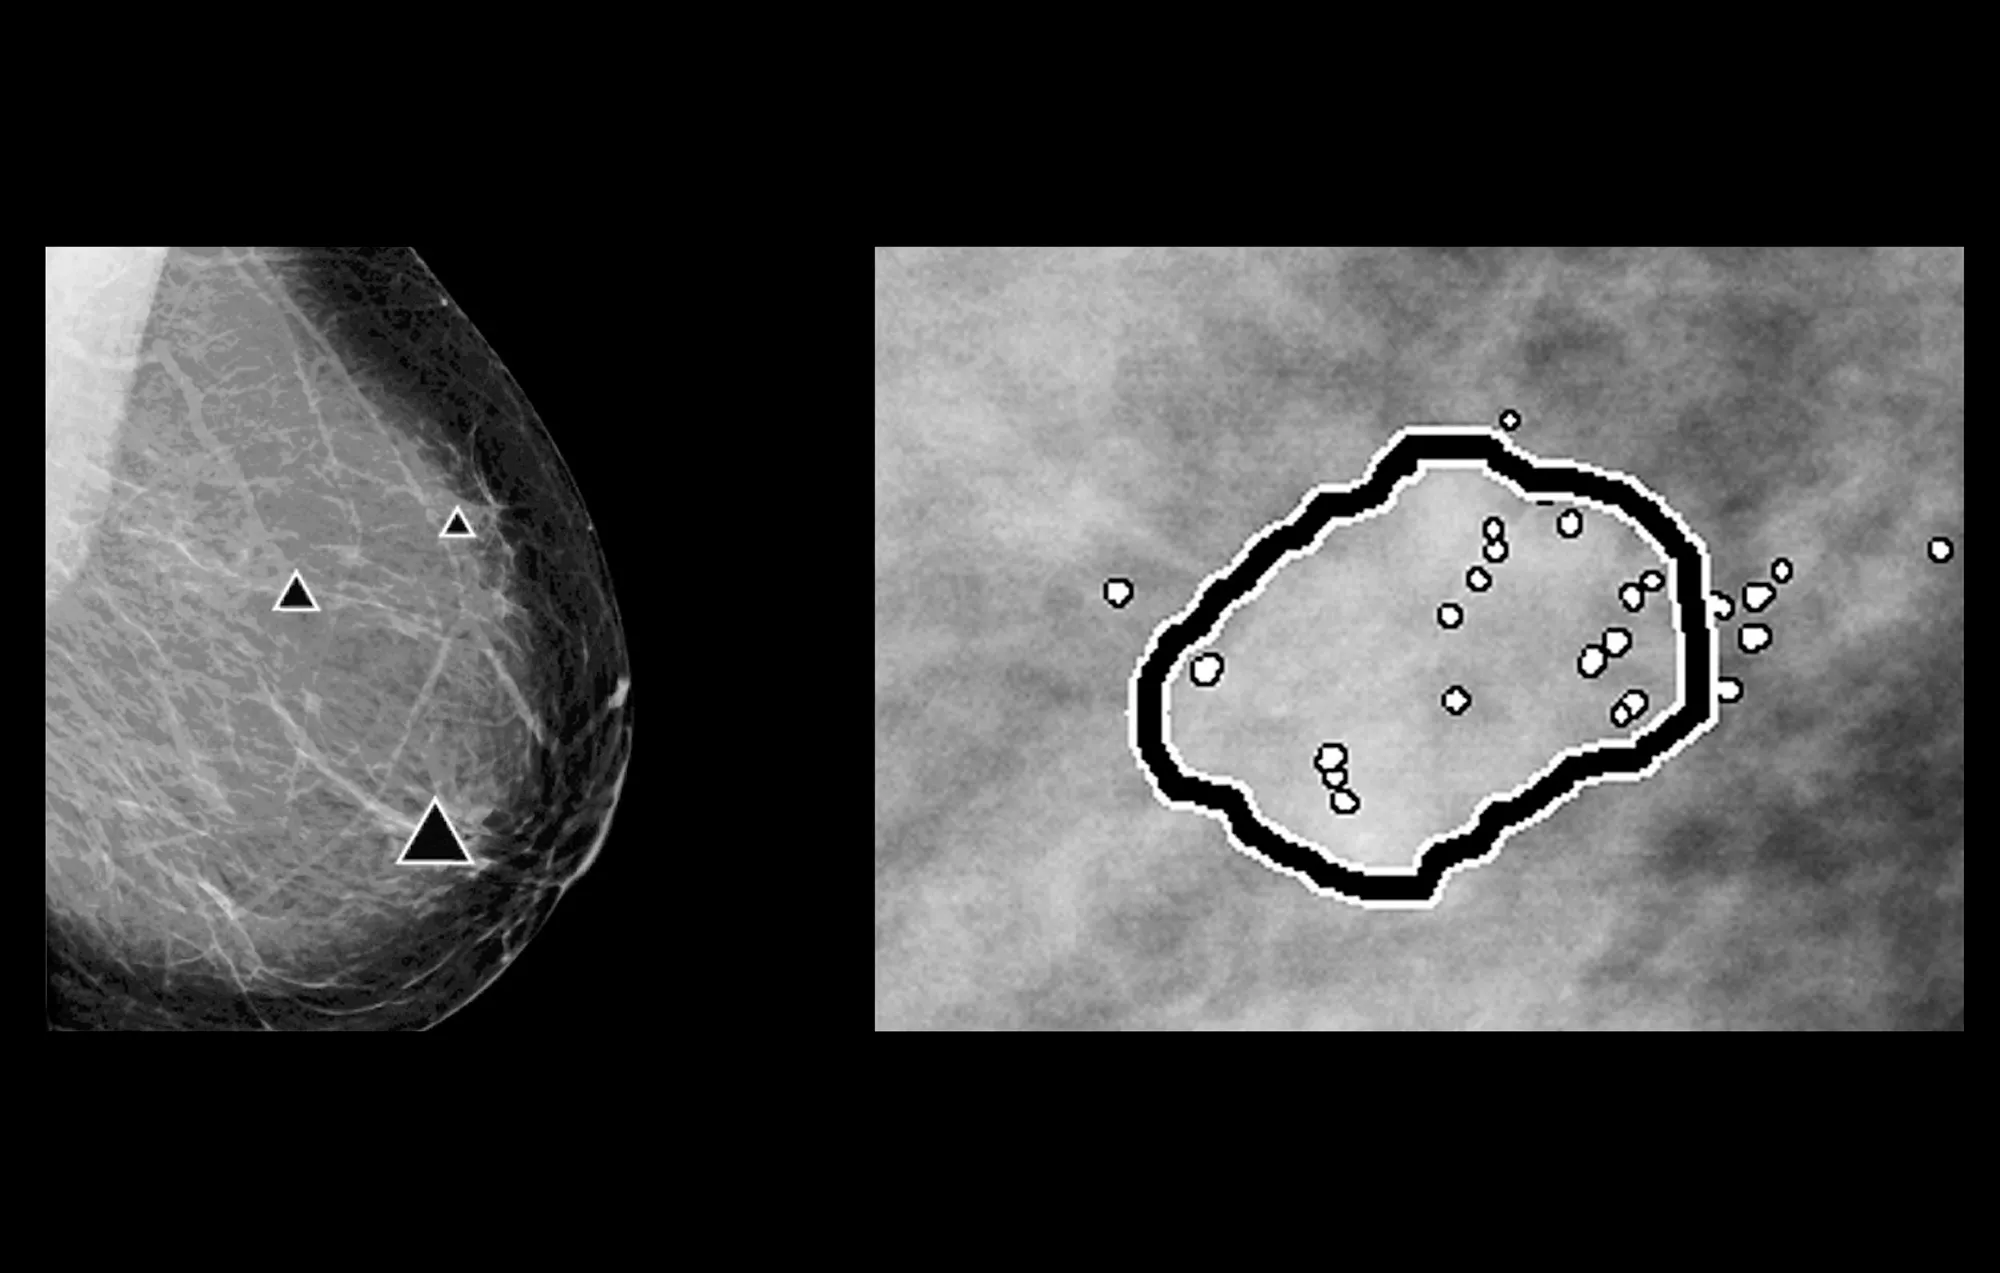

ImageChecker 2D CAD Technology searches digital mammograms for potential microcalcifications and masses, characteristics commonly associated with breast cancer.

- Regions-of-interest are highlighted for the radiologist’s attention

- Delivers highly sensitive results without excessive false-positive marks, streamlining case review2

Image Gallery3